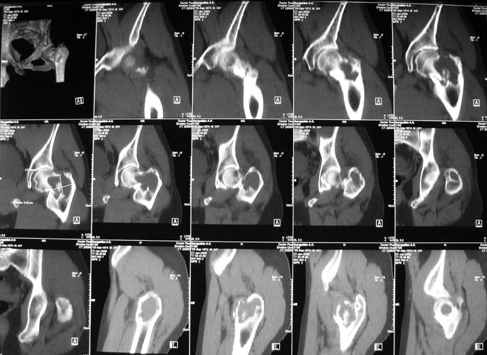

Уважаемые коллеги! Больной (1974 г.р.) травма 26.01.2009г., у пал на ра-боте с высоты своего роста, доставлен в одну из горбольниц Екатеринбурга в травматологическое отделение. На рентгенограмме выявлен патологический перелом чрезвертельной области левого бедра.

Доброкачественная опухоль (ОБК?, энхондрома?), по данным RS. Дополнительно произведено КТ. Наложено скелетное вытяжение.

Прилагаются: рентгенограмма и данные СТ

По данным рентгенограммы и СТ диагноз определить в данном случае нельзя. При дифдиагнозе можно предполагать костную кисту, остеокластому, хондрому; в нашей клинике был подобный случай - гистологически верифицирована хондромиксоидная фиброма.

В настоящий момент прошло около 2 мес., как с консолидацией фрагментов? Возможно будет приемлема внутриочаговая резекция с костной пластикой и внеочаговым остеоситезом. В нашей клинике резекционный дефект обязательно обработали бы инстилляционно жидким азотом